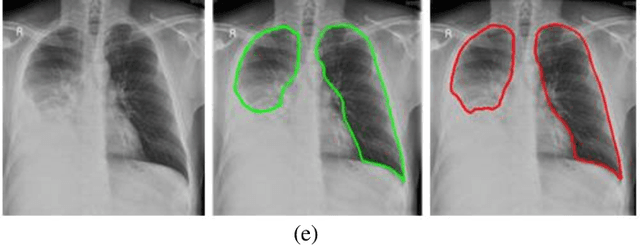

Abstract:With increasing number of COVID-19 cases globally, all the countries are ramping up the testing numbers. While the RT-PCR kits are available in sufficient quantity in several countries, others are facing challenges with limited availability of testing kits and processing centers in remote areas. This has motivated researchers to find alternate methods of testing which are reliable, easily accessible and faster. Chest X-Ray is one of the modalities that is gaining acceptance as a screening modality. Towards this direction, the paper has two primary contributions. Firstly, we present the COVID-19 Multi-Task Network which is an automated end-to-end network for COVID-19 screening. The proposed network not only predicts whether the CXR has COVID-19 features present or not, it also performs semantic segmentation of the regions of interest to make the model explainable. Secondly, with the help of medical professionals, we manually annotate the lung regions of 9000 frontal chest radiographs taken from ChestXray-14, CheXpert and a consolidated COVID-19 dataset. Further, 200 chest radiographs pertaining to COVID-19 patients are also annotated for semantic segmentation. This database will be released to the research community.